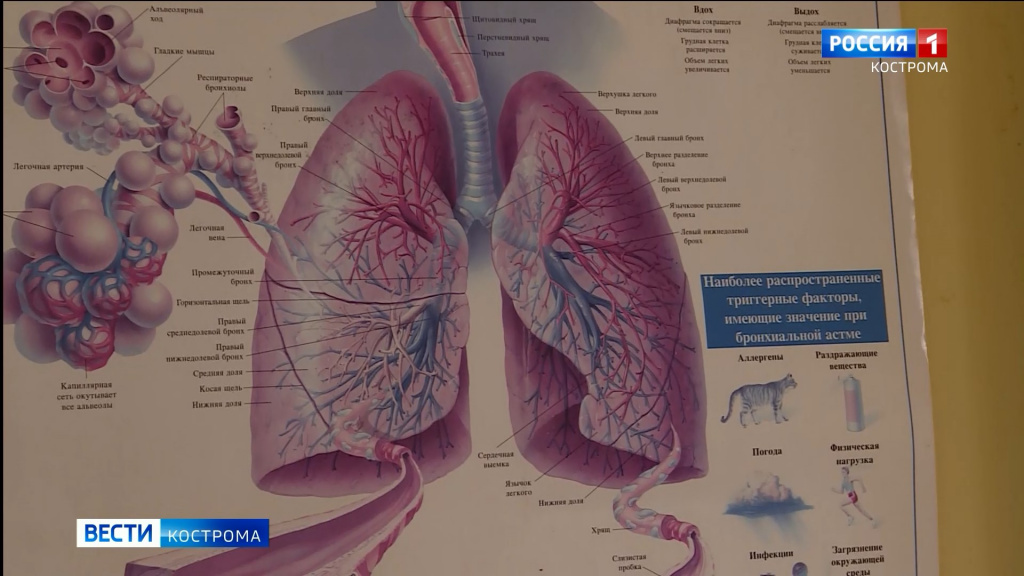

Острая внебольничная пневмония по МКБ-10: признаки и примеры